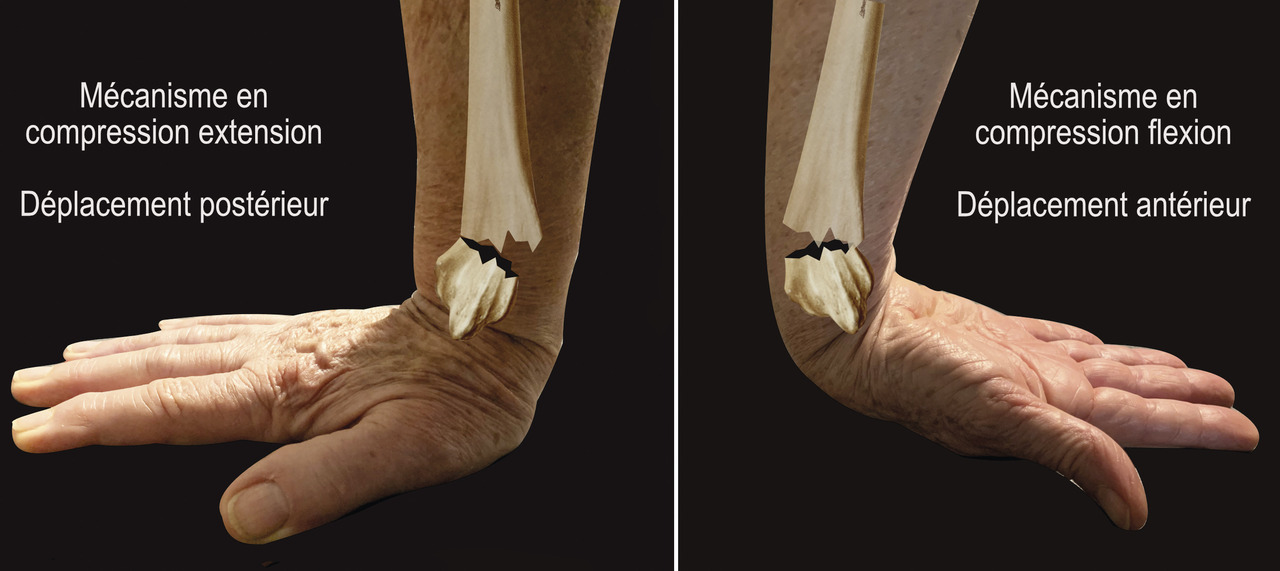

Au niveau métaphysaire le déplacement peut être postérieur ou antérieur (fig. 6). En ce qui concerne le déplacement postérieur, il est important de se souvenir que la surface articulaire regarde vers l’avant. En d’autres termes, dès que cela n’est plus le cas, même si la surface articulaire n’est pas orientée vers l’arrière, il s’agit d’un déplacement postérieur. Classiquement, le déplacement postérieur est lié à un mécanisme dit en compression-­extension, c’est-à-dire une chute sur la main, le poignet étant en extension (fig. 7). Le déplacement est dit antérieur s’il y a une exagération de l’orientation antérieure de l’épiphyse radiale. Ce déplacement est classiquement lié à un mécanisme dit en compression-flexion, c’est-à-dire une chute sur la main, le poignet étant en flexion (fig. 7). La plupart du temps, ce déplacement postérieur ou antérieur s’accompagne également d’un déplacement externe, avec un tassement au niveau de la corticale latérale (fig. 8). Outre le déplacement antérieur, postérieur ou latéral, il est très important d’analyser au niveau du foyer de fracture métaphysaire l’importance de la comminution qui peut être uniquement postérieure, ou antérieure, ou circonférentielle, ce qui conditionne la stabilité de la fracture et oriente vers le type d’ostéosynthèse à réaliser.

L’approche clinique initiale au service d’accueil des urgences ne permet le plus souvent que d’avoir une suspicion diagnostique. La classique déformation du poignet en dos de fourchette (lors des déplacements postérieurs) (fig. 11), loin d’être systématique, permet de renforcer cette suspicion. Le diagnostic positif et descriptif des lésions fracturaires ne sera cependant confirmé que par les examens d’imagerie (radiographies et éventuellement tomodensitométrie).